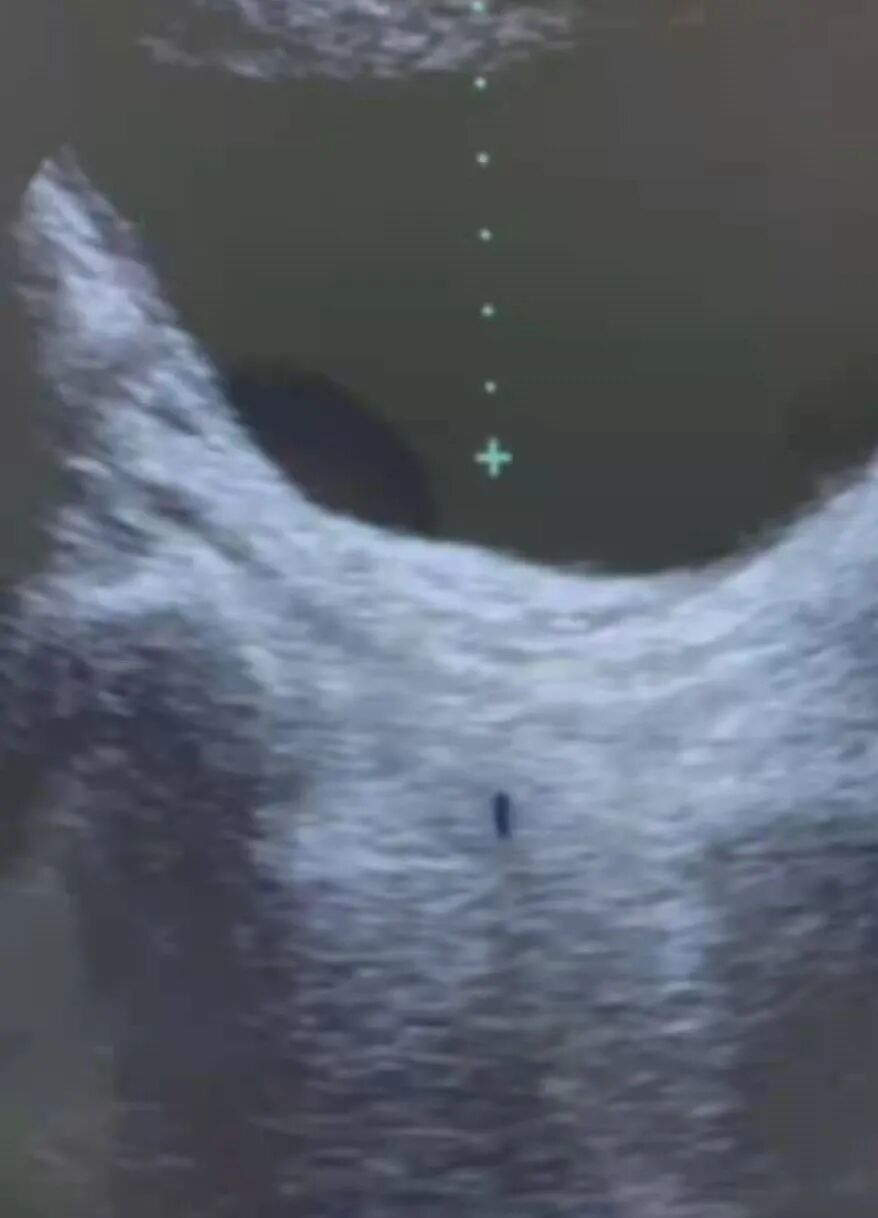

病例:

杨xx:女 ,出生日期:1966年06月04日,民族:汉,族:汉族,职业:农民, 婚姻状况:已婚,药物过敏史:无,病人主诉:左输尿管结石ESWL术后3周复查,现病史:1月前因左腰腹部疼痛,于当地超示左输尿管结石,行ESWL1次,术后无血尿、无排石,1周前来我院复查,B超示左输尿管下段结石伴左肾盂轻度积水,今复诊要求体外冲击波碎石治疗,既往史:无类似发作史.体格检查:(阳性体征、必要的阴性体征)双侧肾区无叩击痛。辅助检查结果:21-07-07本院B超诊断意见:双肾结石左侧输尿管下段结石(10mm)伴左侧肾盂轻度积水.尿液分析:红细胞(RBCU)5[个/u1],白细胞(WBC_UP)3[个/u]。血常规+CRP+凝血四项:正常,诊断:(N13.202)肾积水伴输尿管结石,ESWL术后,诊疗意见:全自动尿液分析.(尿液)\血常规+CRP(静脉血)+凝血四项(血液)\体外冲击波碎石(9.3k*1300次),碎石效果良好,皮肤轻微损伤(肉眼可见出血点),术后有血尿。多饮水,适度运动,注意排石情况,收集结石标本。1周复查,随诊。